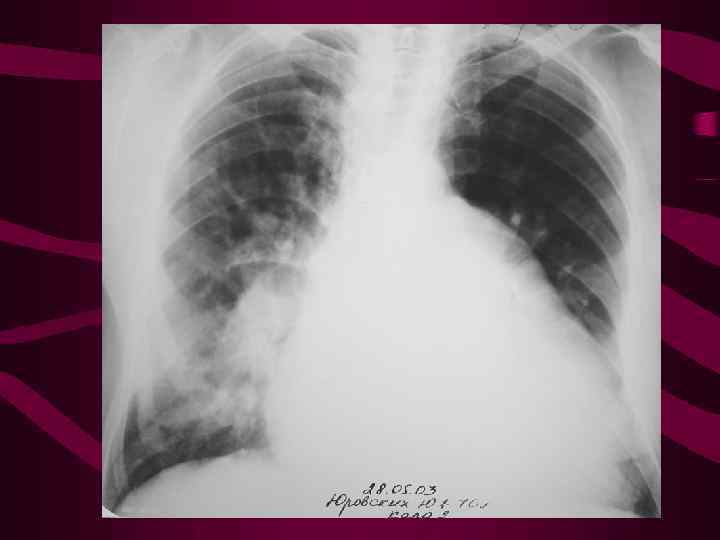

4 - альвеолярный отек легких Изменения соответствуют среднему давлению в левом предсердии свыше 35 мм рт. ст. На фоне венозного застоя с признаками интерстициального отека определяются множетсвенные сливающиеся, разной величины очаговые тени в легких за счет скопления эксудата в альвеолах. Очаговость имеет неравномерную интенсивность и нечеткие очертания, может быть симметричной, двухсторонней, но может быть и односторонней. Нередко выпот в плевральных полостях.

4 - альвеолярный отек легких Изменения соответствуют среднему давлению в левом предсердии свыше 35 мм рт. ст. На фоне венозного застоя с признаками интерстициального отека определяются множетсвенные сливающиеся, разной величины очаговые тени в легких за счет скопления эксудата в альвеолах. Очаговость имеет неравномерную интенсивность и нечеткие очертания, может быть симметричной, двухсторонней, но может быть и односторонней. Нередко выпот в плевральных полостях.

Альвеолярный отек слева

Альвеолярный отек слева